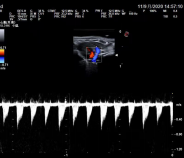

微血管“珊瑚”成像 (MicroV):

采用百胜专利计算方式,在有效保证帧频的前提下,去除背景噪声,降低周边 强回声结构信息干扰,保证清晰可视细小血管和低速血流。具有 5 种成像方式,可 应用于各类探头的不同临床应用。对于无创、快速的检测极低速血流成像有明显帮助, 可应用于:小血管、风湿、脑血管疾病诊断

猫动脉